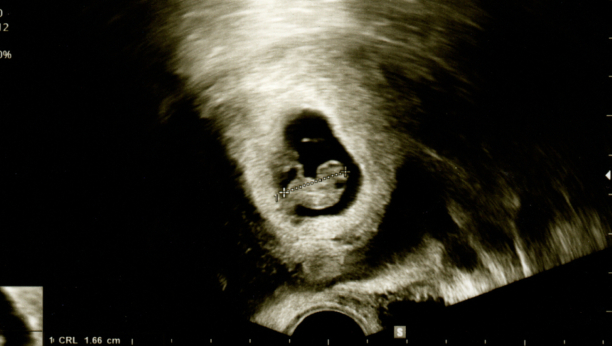

„Nestao je“, rekao joj je doktor. Nekoliko puta je proverio ultrazvuk. „Kako to mislite nestao?“, upitala je. Poslednji put kad je ležala u toj sobi, na pregledu osmonedeljne trudnoće, na snimku su bile dve bebe i dva otkucaja srca.

Kako je moguće da je pet nedelja kasnije jedno od njene dece nestalo? Nije imala krvarenje, grčeve, nikakve simptome koji bi ukazivali da nešto nije u redu. „To se zove sindrom blizanca koji nestaje“, rekao je doktor. „Jedan blizanac 'apsorbuje' drugog“.